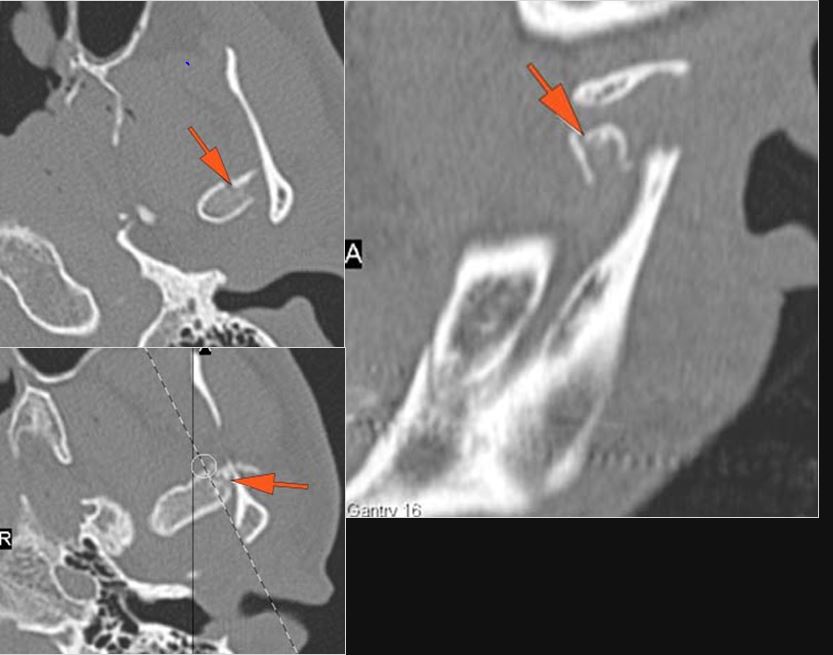

The condylar head and fossa as well as the temporomandibular joint space are fractured and/or dislocated. [Yes/No]

There is condylar fracture either within or outside of the joint capsule, or with or without involvement of the articular surface of the condylar head. [Yes/No]

There is evidence of radiodense intra-articular osteochondral fragments. [Yes/No]

There is bony injury or displacement of the external auditory canal and/or other evidence of temporal bone injury. [Yes/No]